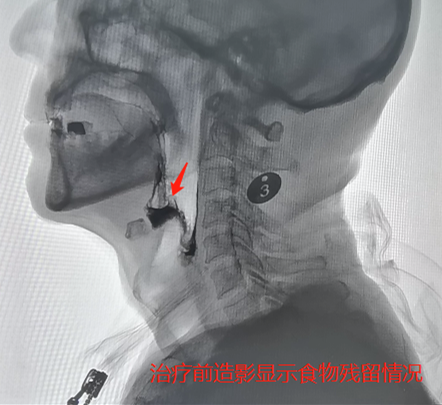

91岁的尤爷爷身体还算硬朗,可最近老人总是食欲差、乏力,还时不时地发烧,家人觉得很蹊跷,老人最近并没有受寒,应该不是着凉感冒,遂将尤爷爷送到湖南省人民医院。经检查,尤爷爷咽部有大量食物残留,因吞咽障碍导致隐性误吸引发了肺炎。

尤爷爷被收入康复医学科二病区,经过口颜面感觉运动训练、气道保护训练、体位调整、姿势代偿、食物调配等个体化治疗后,他的咽部食物残留、误吸情况得到明显改善,营养状况持续好转,肺部感染也得到了有效控制,今日顺利出院。